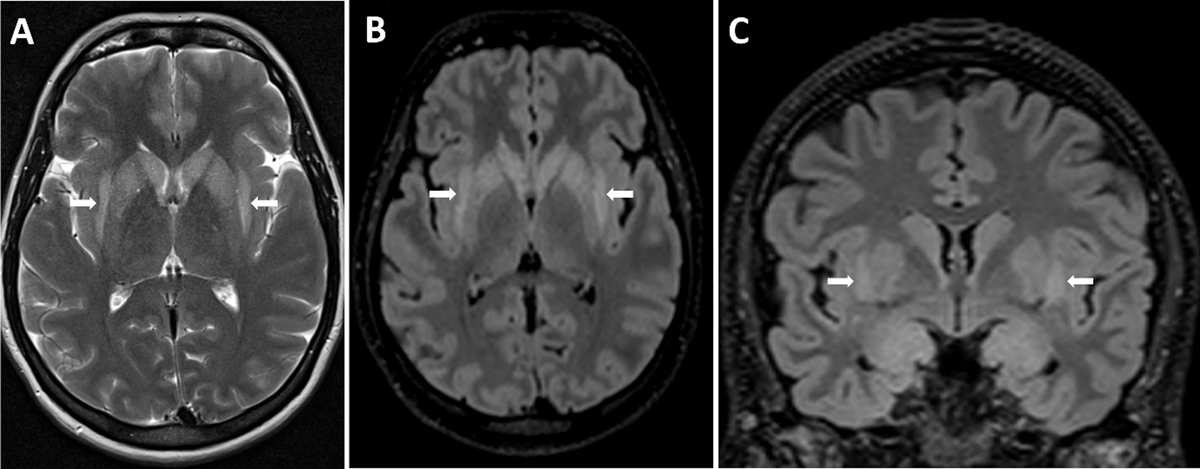

A 39-year-old woman who recently suffered an influenza-infection presented at the ER because of confusion, hallucinations, and progressive neurological decline. During her hospitalisation, she developed focal myoclonic epilepsy which transformed into status epilepticus. Magnetic resonance imaging (MRI) of the brain showed bilateral T2-hyperintense changes in the mesiotemporal structures on axial FLAIR-weighted images (Figure 1, arrows) and on axial and coronal T2-weighted images (Figure 2A–B respectively, arrows). Additionally, a bilateral T2-hyperintense claustrum was seen on axial T2 and axial and coronal FLAIR-weighted images (Figure 3A–C respectively, arrows). Lumbar puncture showed mild pleiocytosis and mildly elevated protein levels. Viral serological and PCR tests were negative. Clinical findings without detection of an acute seizure cause are compatible with febrile infection-related epilepsy syndrome.

Figure 3

Another finding that was present in our patient, is the claustrum sign: bilateral T2-hyperintense signal changes in the claustrum. The claustrum sign is neither diagnostic nor specific for NORSE or FIRES however and has also been reported in other diseases such as acute necrotizing encephalopathy, COVID-19-related encephalopathy, and immune effector cell-associated neurotoxicity syndrome [1]. What all these entities have in common is a characterised cytokine storm, so the claustrum sign might be a radiological marker of cytokine-mediated neuro-inflammation.